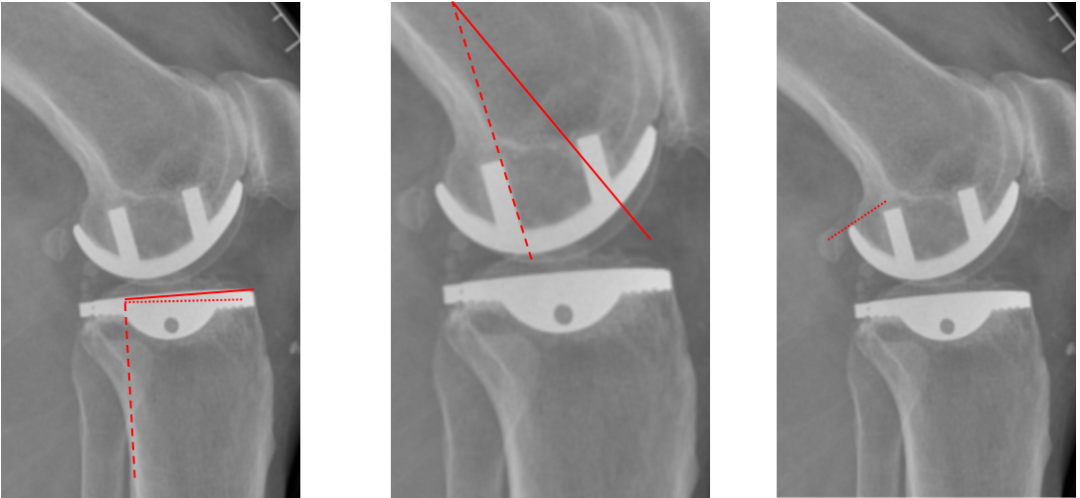

侧位片标准胫骨和股骨假体位置

侧位片假体位置:胫骨假体后倾3°,与胫骨平台前后缘齐平,股骨假体后倾40°,假体后缘与股骨后髁齐平。

股骨假体偏大且过度屈曲

侧位片假体位置:股骨假体后倾45°,假体后缘超出股骨后髁3mm, 胫骨假体后倾3°,与胫骨平台前后缘齐平。